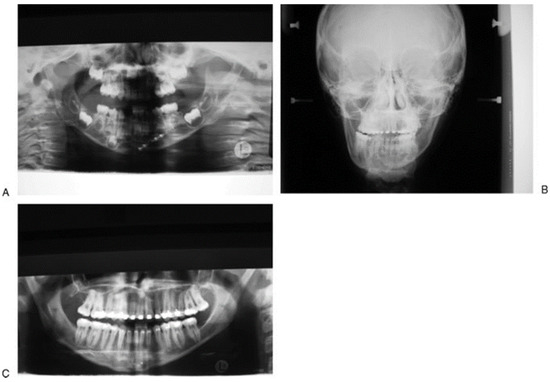

Loss of permanent dentition may result from direct injury to the erupted tooth or damage to tooth buds. Iatrogenic damage to tooth buds may occur during rigid fixation with screws. Bioresorbable fixation can be used, but we prefer the use of titanium plates and screws [44]. We remove them at 6 months to prevent long-term growth disturbance and to allow ease of removal before they become encased in bone. This is especially important in mandibular angle fractures where a plate may interfere with future mandibular osteotomies. A Champy-style plate may interfere with the eruption of the third molar if not removed early (Figure 9). Nerve injury at the time of injury or during bony reduction may persist long term, although children are less likely to be symptomatic than adults.

Figure 9. (A,B) This patient sustained a blow to the right side of the face while playing ice hockey. There was an undisplaced right parasymphyseal fracture and a displaced angle fracture on the left side that was treated with a Champy-style plate. This will be removed to allow eruption of the third molar.